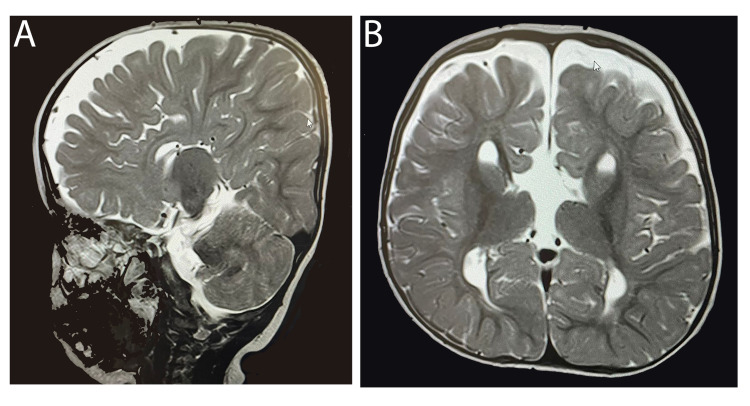

一名 14 个月大的女童,有全身发育迟缓、畸形特征(眼距过远、眼球突出、上睑下垂、小颌畸形)和弱视病史,被转诊至佳学基因遗传病罕见病基因检测案例协作单位。就诊原因是言语和语言发育迟缓。 她的父母是一级近亲,被诊断患有双侧重度至极度SNHL,并在 9 个月大时安装了双侧助听器。 然而,在随访中没有发现使用助听器有明显的好处。 磁共振成像 (MRI) 显示胼胝体完全发育不全(图 1)。 此外,全外显子组测序显示 LRP2 基因突变,证实了 DBS 的诊断。 在 18 个月大时,她的智商测试成绩为 75 分。

病例 1 的 MRI:(A) 矢状切面 (B) 冠状切面显示胼胝体完全发育不全